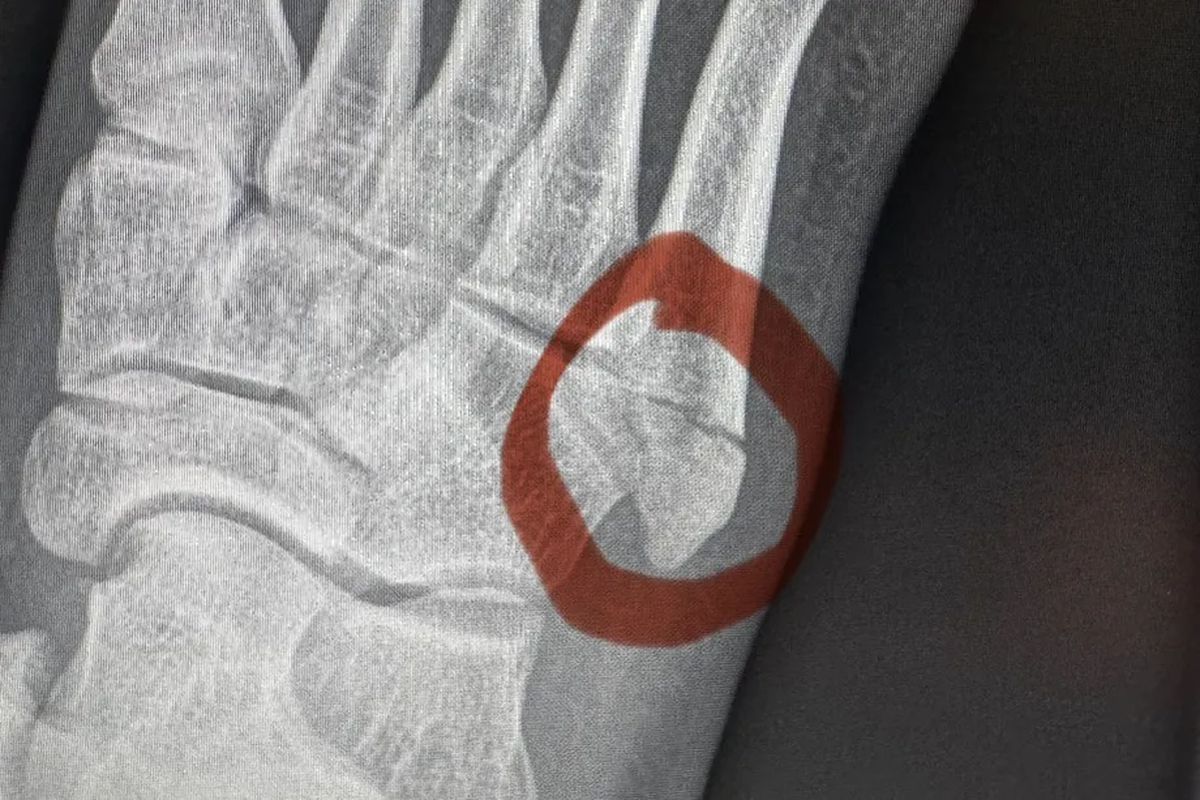

Опубликован снимок перелома стопы Манэла Капе перед UFC 317

Претендентский бой в наилегчайшем весе между Брэндоном Ройвалом и Манэлом Капе на UFC 317 сорвался — португалец получил перелом стопы во время подготовки. Он подтвердил отмену поединка в соцсетях:

«С сожалением сообщаю, что не смогу выступить на UFC 317. Во время тренировки я сломал стопу, врачи рекомендовали операцию и полное восстановление».